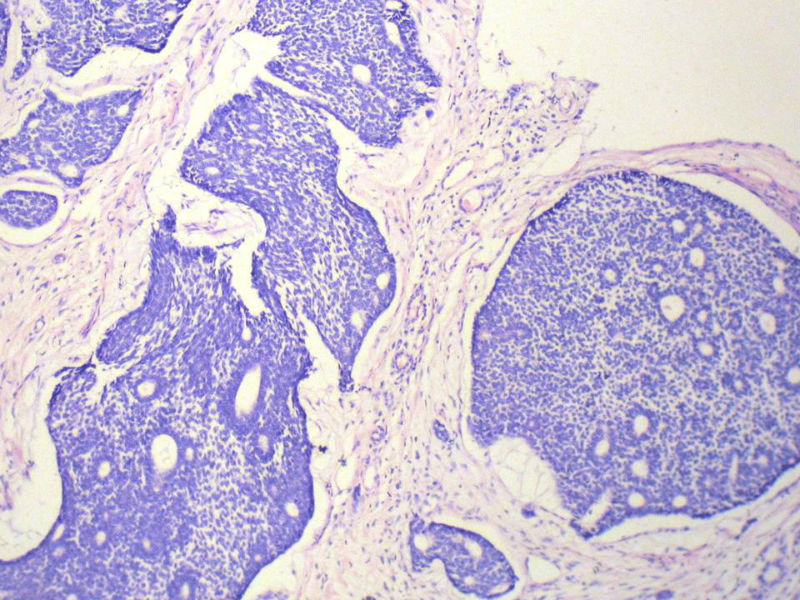

男,76岁,鼻塞两个月,CT提示左上颌窦占位,局部骨质破坏,口腔硬腭下降,局部活检。

左上颌窦占位图4

名称:图4

描述:幻灯片5

腺样囊性癌

腺样囊性癌,图像很典型的